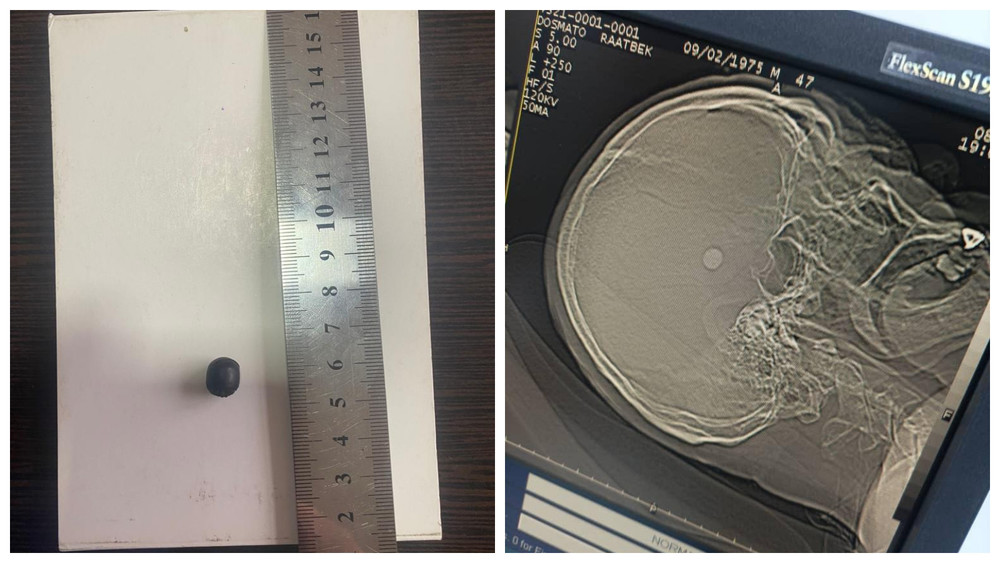

Жалал-Абадда шок абалда ооруканага түшкөн адамдын башынан ок алып чыгышты. Учурда абалы кандай?